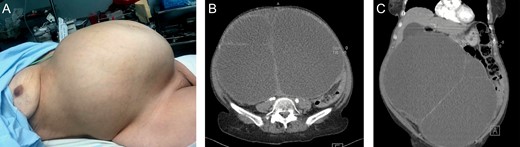

Patient is a 64-year-old female with a past medical history of hysterectomy and a right oophorectomy. She presented to our department with a four-year history of abdominal mass in her lower abdomen that has grown to gigantic proportions, however, due to a lack of adequate access to healthcare facilities and a fear of a possible surgery caused her to not seek any medical attention. Nonetheless, in the previous 4 months, she noticed pain around the mass, severe weight loss and recurrent episodes of postprandial vomit. On clinical examination a 40 × 34 cm hard, nontender abdominal mass was found in her abdomen, (Fig. 1A) the tumor was hard in consistency, and non-mobile. Auscultation of the abdomen revealed normal bowel sounds. Laboratory data including were normal, however CA-125 was slightly elevated.

A: Giant abdominal mass. B: Contrast-enhanced CT: Giant mass with heterogeneous contrast enhancement on its wall, and filled with a heterogeneous fluid. C: Contrast-enhanced CT: Giant mass, that displaced most of the abdominal contents.

A contrast-enhanced computed tomography (CT), revealed a 32 × 34 × 29 cm, giant mass with heterogeneous contrast enhancement on its wall, it was filled with a heterogeneous fluid and solid peripheral zones with some calcifications, it appeared to arise from the left adnexa and it displaced most of the abdominal contents. Yet, it did not invade any adjacent structures and no other masses were observed. (Fig. 1B and C)